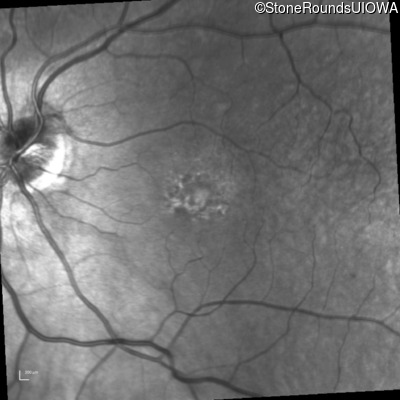

Infrared Fundus Photograph - Right - 20/100

Exemplar